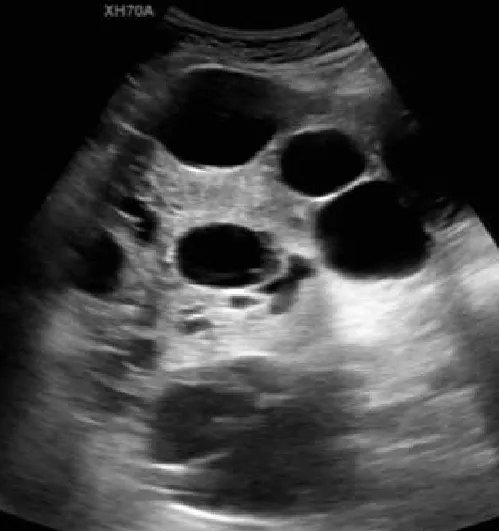

多囊肝

● 肝内无数个无回声区。

● 大者边界清,形态一般欠规整。

● 内透声好。

● 后方结构(后壁)回声增强。

● 无囊肿部位肝组织回声增强增粗。